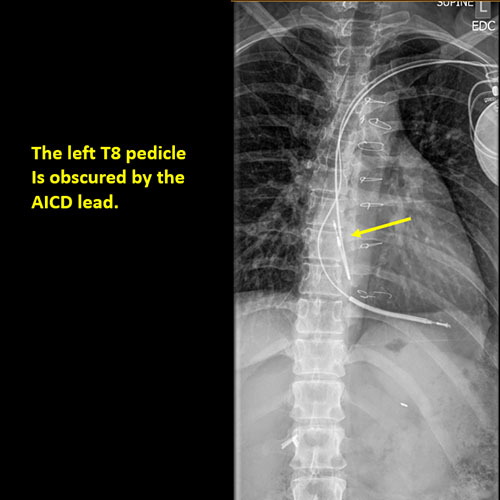

There is a foreign body or there are post surgical changes of the bones or soft tissues of the included neck, thorax, or abdomen. |

No | NA |

There is an abnormality or complication of post surgical hardware/device. |

N/A | NA |